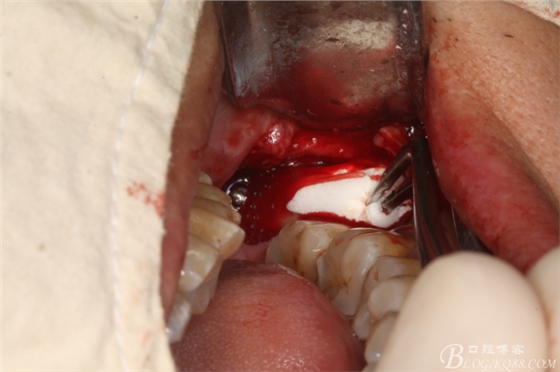

圖三、完全暴露38牙根和牙冠

圖4.橫斷牙根和牙冠

圖10.創(chuàng)口內(nèi)放置膠原蛋白海綿